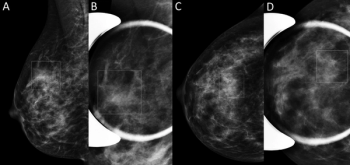

Combining DBT and synthetic mammography can mean less follow-up imaging for women with non-dense breasts – but not necessarily for women with dense tissue.

Digital breast tomosynthesis improves cancer detection rates and reduces recalls, but not for all women.